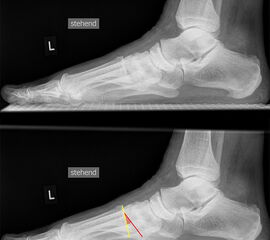

Fuß seitlich ohne Belastung

Positionierung:

• Patient befindet sich in Seitenlage auf dem Röntgentisch, der zu untersuchende Fuß befindet sich unten.

• Der Fuß liegt seitlich auf der Röntgenkassette.

• Der Zentralstrahl fokussiert auf das Kalkaneokuboidalgelenk knapp cranial der Basis des Os metatarsale V.

• Die Röhre ist mit 0° vertikal eingestellt.

Kennzeichen des Röntgenbildes:

• Immer wenn die Tibia nicht zentral über dem Talus steht, handelt es sich um unbelastete Aufnahmen.

Besondere Bemerkungen zum Beispielbild:

• Der Patient erlitt ein Mittelfußtrauma. Unter Frakturverdacht erfolgten die unbelasteten Aufnahmen.

• Die Frakturlinie im Os cuneiforme I ist in der lateralen Aufnahme schwer erkennbar.

• Unauffällige Abbildung des restlichen Fußskeletts.

• Für die OP-Planung erfolgte dann noch ein Schnittbildverfahren.